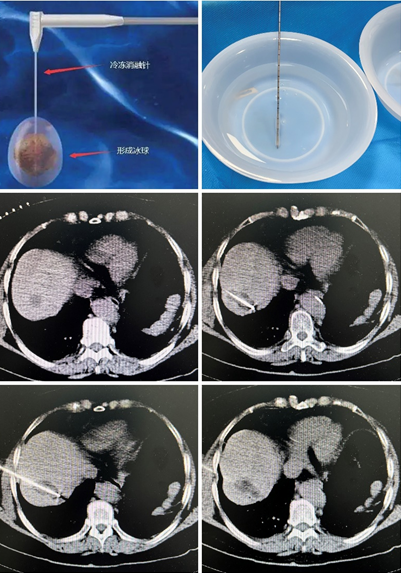

患者系老年女性,肝胆外科肝内胆管癌切除术后,近期查体发现肝脏新增肿瘤结节。在肝胆外科张智勇主任医师、常虎林副主任医师及介入科陈思攀医师共同讨论并与家属充分沟通后,最终选择了更微创、安全的“氩氦刀”冷冻消融治疗。整个治疗过程在CT室进行,通过病灶扫描、穿刺定位、冷冻消融、扫描复查等一系列过程,治疗团队顺利完成冷冻消融治疗,患者全程清醒,且无明显不适。从CT图像中清晰看出,冷冻消融针精准命中肿瘤结节,在消融针前端反复冷冻及复温的作用下,完全覆盖肿瘤区域,彻底“狙杀”肿瘤,达到预期治疗目标。